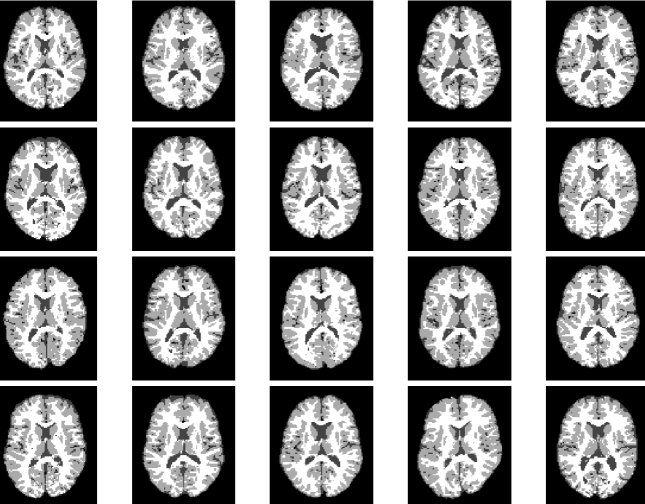

In this paper, we aim to segment an image degraded by blur and Poisson noise. We adopt a smoothing-and-thresholding (SaT) segmentation framework that finds a piecewise-smooth solution, followed by k𝑘k-means clustering to segment the image. Specifically for the image smoothing step, we replace the least-squares fidelity for Gaussian noise in the Mumford-Shah model with a maximum posterior (MAP) term to deal with Poisson noise and we incorporate the weighted difference of anisotropic and isotropic total variation (AITV) as a regularization to promote the sparsity of image gradients. For such a nonconvex model, we develop a specific splitting scheme and utilize a proximal operator to apply the alternating direction method of multipliers (ADMM). Convergence analysis is provided to validate the efficacy of the ADMM scheme. Numerical experiments on various segmentation scenarios (grayscale/color and multiphase) showcase that our proposed method outperforms a number of segmentation methods, including the original SaT.

Image segmentation partitions an image into multiple, coherent regions, where pixels of one region share similar characteristics such as colors, textures, and edges. It remains an important yet challenging problem in computer vision that has various applications, including magnetic resonance imaging [26, 40, 62] and microscopy [7, 81]. One of the most fundamental models for image segmentation is the Mumford-Shah model [50] because of its robustness to noise. Given an input image f:Ω:𝑓Ωf:\Omega\rightarrow\mathbb{R} defined on an open, bounded, and connected domain Ω2Ωsuperscript2\Omega\subset\mathbb{R}^{2}, the Mumford-Shah model is formulated as

• We conduct numerical experiments on various grayscale/color images to demonstrate the effectiveness of the proposed approach.